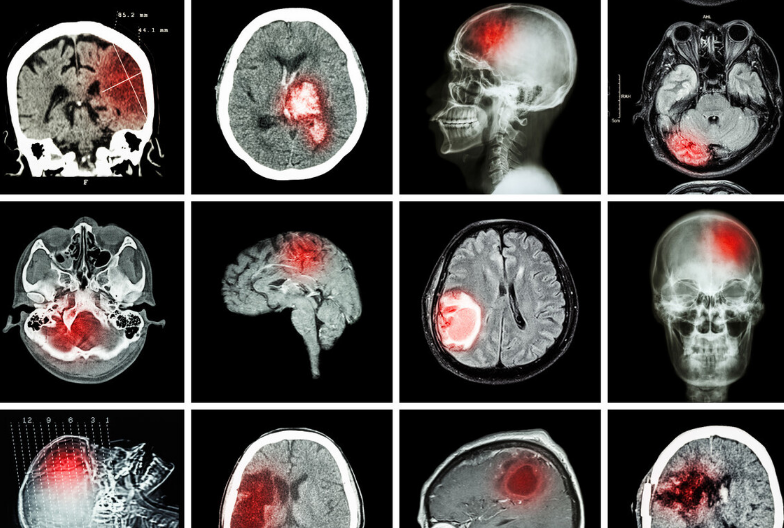

脑梗是由于脑部血管被堵塞,养分和血液不能及时地供应到大脑,造成大脑神经组织出现休克坏死,如果救治的不及时,很可能威胁患者生命,但是有些患者因为梗死的面积较大,就算得到及时救治,还是会留下偏瘫,半身不遂的后遗症。